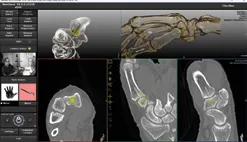

Plan optimal cup position and axis with guided trajectory

Import CT/CBCT, select implant and define the ideal position and orientation

Attach the reference marker and complete quick 3-point bone registration

Follow the guided trajectory with probe and drill; ream precisely over the K-wire

Insert the trapezium cup with confidence along the planned axis, aligned with the stem